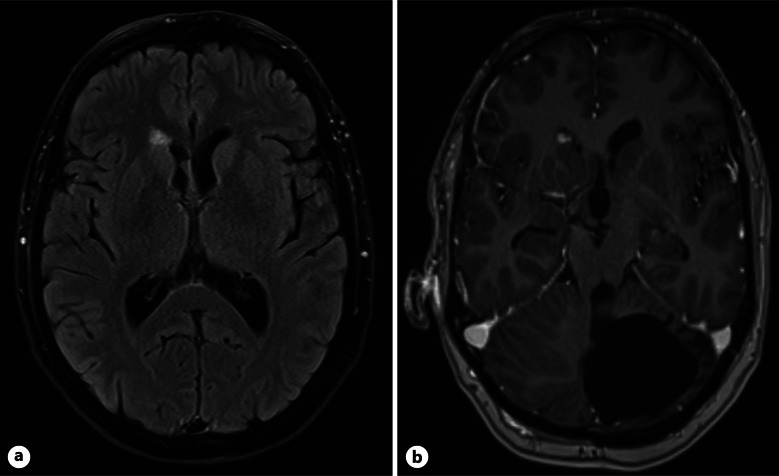

Case summary: A 46-year-old female presented with a 3-month history of worsening back pain. Reduced sensation on the right side in L1, L2, and per rectum was found on examination. MRI displayed a L3 IDEM mass. Background was significant for childhood PA, debulked at age 8 and 13. Right L3 hemilaminectomy and subtotal resection was performed. The mass was found to be composed of pleomorphic astroglial cells and was glial fibrillary acidic protein-positive with a fusion between exon 16 of KIAA1549 and exon 9 of BRAF. A recurrence of pilocytic astrocytoma in the lumbar spine was diagnosed, over 38 years after previous treatment.

Abstract Image